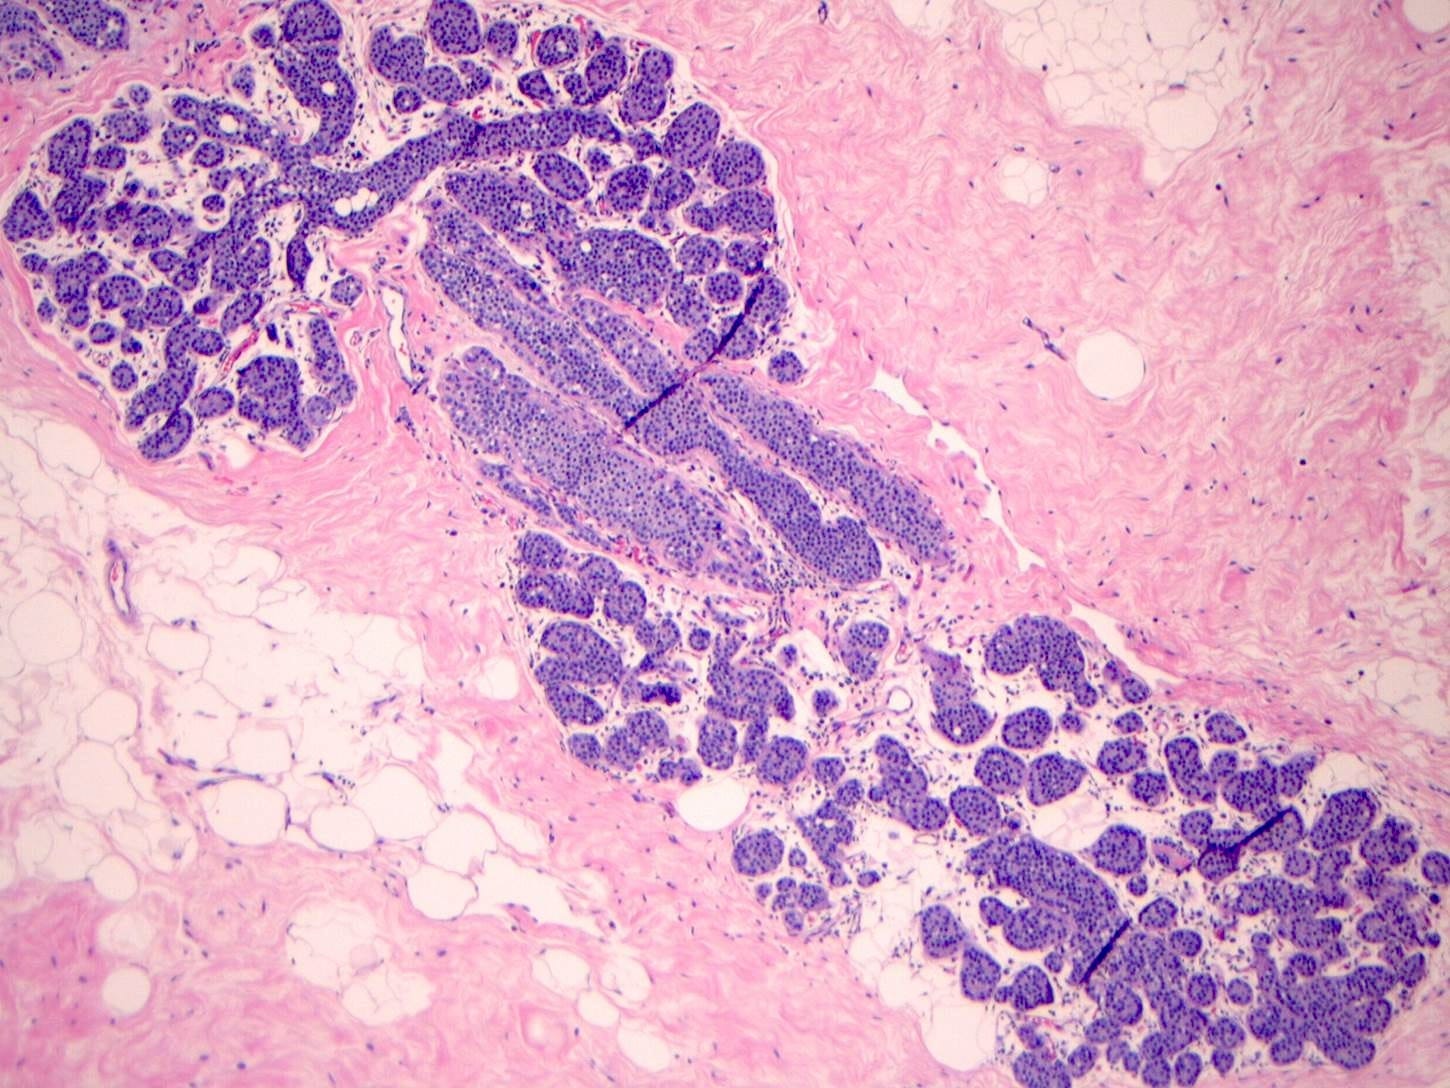

Florid lobular carcinoma in situ - microscopic images

Precursor of classic lobular carcinoma - florid lobular carcinoma in situ

Florid LCIS is a rare (< 5% of LCIS) nonclassical or variant form of lobular carcinoma in situ in which acini and ducts are markedly distended with little to no intervening stroma. It may have a mass-like architecture and includes cells with cytologic features of classic LCIS (type A or type B cells) with or without comedonecrosis and calcifications. Most cases are associated with classic LCIS or atypical lobular hyperplasia (ALH).

Florid LCIS has features of a high risk precursor lesion of invasive carcinoma including a higher upgrade rate, increased association with invasive carcinoma and more genetic complexity compared to classic LCIS.

In contrast to classic LCIS, complete surgical excision of florid LCIS is recommended.